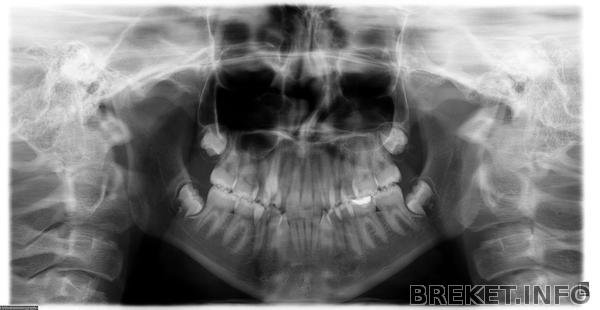

Всем привет Возникла такая проблема. Мне сняли брекеты почти уже 5 месяцев назад. При лечении удалили 4 четверки. Зубы мудрости не трогали вообще и не обсуждали. Но вдруг они стали расти!На удивление,ничего не болит,не тянет,не опухло. Случайно заметила,зубы вроде все на месте Паника В январе нужно записываться к врачу на плановый осмотр. Очень пугает такая ситуация. Может ли случиться рецидив? Капы ношу,ретейнеры стоят. Нужно или же можно их удалить?